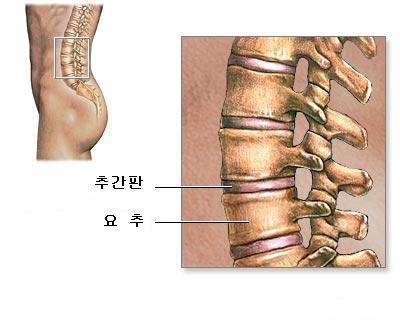

미국 캘리포니아 샌프란시스코 대학병원 정형외과 의사인 Livermore 교수의 발표에 따르면 급성 요추염좌는 요통환자의 약 5%정도를 차지한다고 하는데, 요추 염좌는 발목이 삐긋 했듯이 허리가 삐었다는 말이며, 척추에 있는 관절은 척추체 사이에 관절인 추간판 즉 흔히 말하는 디스크와 함께 후방 척추관절로 양쪽에 있는 추간관절(facet joint)이 척추를 뒤쪽에서 고리처럼 연결되어있다. 요추 염좌는 흔히 일어나는 일이지만 단순히 근육이 손상된 경우부터 인대가 손상된 경우 (흔히 이럴 때 인대가 늘어났다고 한다), 추간판에서 수핵을 둘러싸는 막인 섬유륜의 일부 가 찢어지는 경우 등 여러 가지 상태가 있는데, 근육만 다친 경우라면 며칠 안 가서 치료 가 되지만 추간판에서 수핵을 둘러싸는 섬유륜의 일부가 찢어진 경우라면 추간판 탈출증(허리 디스크병)의 원인이 된다. 또한 외력에 의해 척추 후방부의 추간관절과 관절주위의 인대가 손상이 생겨 심한 요통이 발생하며, 이 추간관절은 매우 제한된 범위의 관절운동만을 할 수 있어 생리학적으로 인대와 관절면이 견딜수 없는 외력이 허리에 가해지면 인대와 관절면이 손상받고, 작은 허리 움직임만으로도 손상된 관절면을 건드리게 되어 심한 통증과 허리의 운동장애가 발생하게 되는 것이다. 대부분 준비되지 않은 상태에서 무거운 물건을 허리의 힘으로만 들어올리려 했을때, 원하는 동작과 반대되는 역동작을 갑자기 하려고 할 때, 부지불식간에 큰 외력에 의해 허리가 갑자기 굽혀지는 동작이 발생될 때 (안전 밸트 착용시 차의 급정거), 앉은 자세에서 바닥의 물건을 주우려고 몸을 뒤틀어 숙였을 때가 가장 흔한 원인이 된다. 악 소리도 못하고 입이 딱 벌어질 정도로 요통이 발생하며 그 자리에서 꼼짝도 못할 정도로 매우 심한 경우가 많고, 허리를 조금만 움직이려해도 몹시 괴로운 요통이 발생하며 가만히 있더라도 허리 근육이 뻣뻣하게 굳어 가는 느낌이 든다.